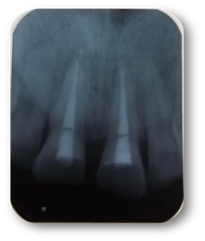

Paciente femenino de 15 años, se presenta a consulta con traumatismo de hace aproximadamente 6 años, comenta haberse golpeado en el piso, acude a dentista particular donde colocaron una pasta.

Diagnóstico: lesión periapical asintomática del OD 1.1, el cual se determinó mediante pruebas radiográficas y de sensibilidad.

Tratamiento: se inició tomando longitud de trabajo 18 mm, se irrigó con NaOCl fueron 3 jeringas por conducto, se colocó pasta doble antibiótica (ciprofloxacina y metronidazol). Se dio una segunda cita donde retiramos la pasta, se secó con puntas de papel, se indujo el sangrado para formar coágulo con una lima #45, se colocó Gelfoam y después MTA blanco todo en la parte cervical del OD, colocamos algodón húmedo, teflón y cemento Ionómero de Vidrio como obturación provisional.

Resultados: Con este tratamiento se espera la resolución de la lesión periapical y el cierre apical del conducto.